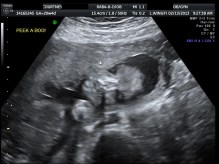

ULTRASOUND_3 February 16, 2013 by Courtney Leave a comment ← Previous Image Next Image → 20w4d – sweet little face! Like Loading...